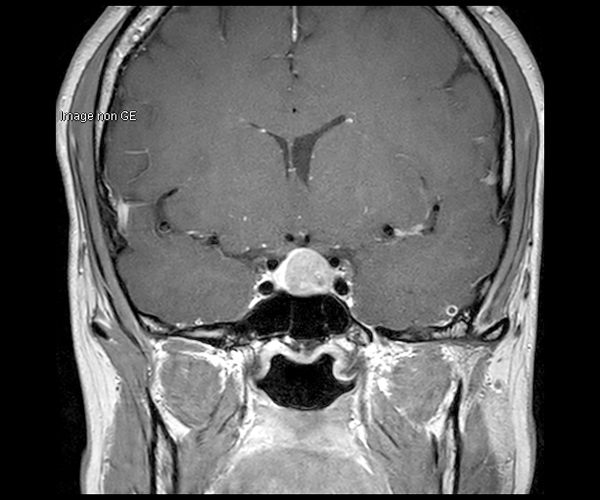

Concernant l’imagerie cérébrale, l’IRM 3T permet d’augmenter la sensibilité de détection de lésions ischémiques aiguës de petite taille, notamment chez les patients adressés pour accident ischémique transitoire (accident vasculaire cérébral), grâce à la séquence de diffusion dont le signal et la résolution sont augmentés.

L’amélioration de la résolution spatiale s’applique à l’exploration morphologique des hippocampes dans le diagnostic de la maladie d’Alzheimer, à la détection de petites lésions de sclérose en plaques ou de métastases, à l’étude fine du cortex dans les épilepsies.

L’augmentation de l’effet de susceptibilité magnétique à plus haut champ permet d’améliorer la détection des hémorragies et est utilisé également dans l’imagerie de perfusion (tumeurs) et l’IRM fonctionnelle (BOLD). L’allongement du T1 à plus haut champ entraîne une meilleure saturation des tissus statiques et par conséquent une augmentation du contraste sang/tissus dans l’AngioIRM.